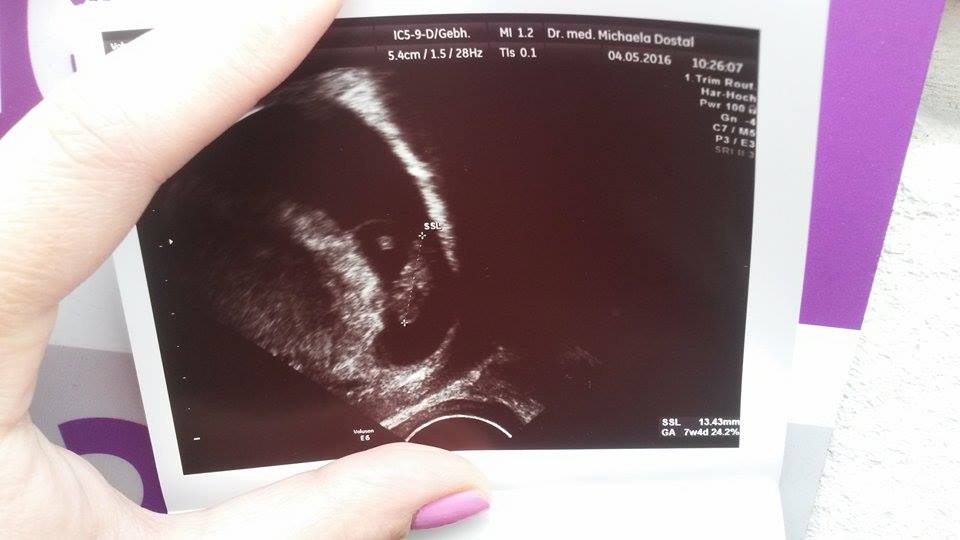

Taak baby, uz mam prvu kontrolu za sebou ☺️ Vsetko je v poriadku, len som dufala ze uz bude vidiet babo. Videli sme zatial len dutinku a zltkovy vak, vraj normalny nalez. Idem zas o tyzden, snad uz bude daco vidiet .

@gynevra Aj ja som práve dnes bola u doktorky a tiež bolo vidno len málinko 🙂 Ale už bolo vidieť aspoň biť srdiečko 🙂 Kráásne.

@gynevra aj ja idem dnes poobede na kontrolu , mala by som byt tiež v 7 tt ako ty 😉 . Pred 2 týždňami som bola na 1. sone a tam bol vidieť len gestačny vak. Dufala som že dnes už niečo viac bude vidieť , ale aj zltkovy vak poteší 😅 . A kedy máš termín ? Držím palce aby o týždeň bolo už aj srdiečko 🙂

@19871987 Mne dala tie snímky bez toho, aby som si ich pýtala. Dala mi snímku aj minule, keď tam bolo fakt vidno len čiernu bodku. Ale ja žijem v Nemecku, možno tu to lekári robia automaticky a na Slovensku nie,,, tak neviem.